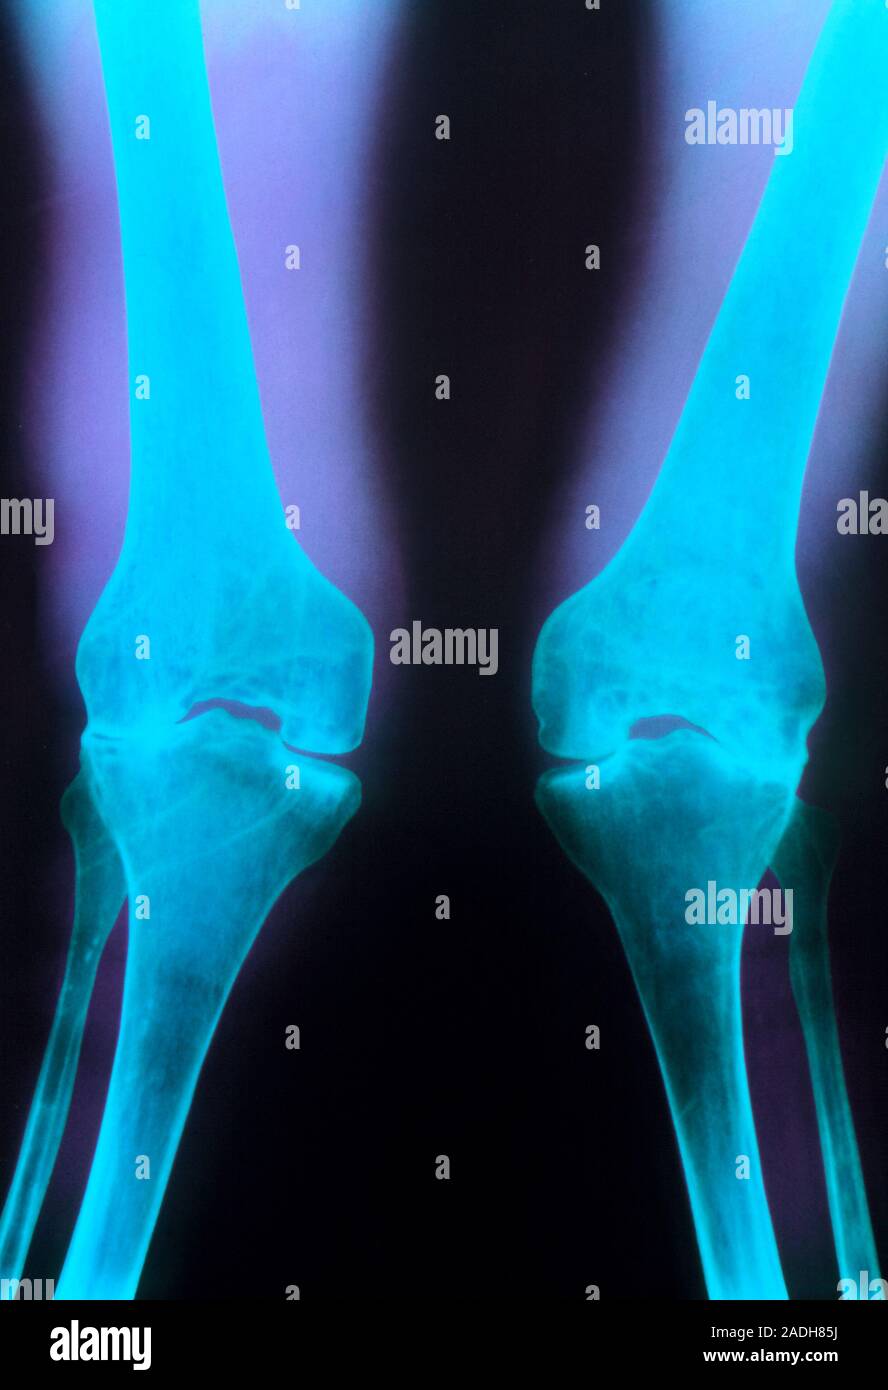

From www.alamy.es

La artritis en las rodillas. Color de rayos X de la deformación de las Que Causa La Artritis En Las Rodillas esta forma más común de artritis afecta principalmente a las articulaciones de las manos, las rodillas, las caderas y la columna vertebral. si experimenta dolor, hinchazón y rigidez en las rodillas, es posible que tenga uno de los siguientes tipos de artritis o afecciones. La artritis de rodilla, también conocida como osteoartritis de rodilla, es una enfermedad degenerativa.. Que Causa La Artritis En Las Rodillas.